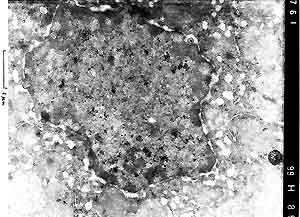

- Case 22-4. Liver (per contributor) TEM. Scattered

within the nucleus are multiple, 100nm diameter, viral particles

(central nucleoid surrounded by a capsid = [nucleocapsid]). Occasional

virions, 150-200nm in diameter, are acquiring an envelope from

the inner nuclear membrane.

- Electron microscopy of liver tissue revealed numerous viral

particles with nucleocapsid and characteristic symmetry within

nuclei of hepatocytes in the periphery of the necrotic foci.

The viral particles measured approximately 100 nm in diameter.

Occasionally virions, 150 to 200 nm in diameter, obtaining an

envelope from the inner membrane of the nucleus could be seen.

Histologic and electron microscopic findings are consistent with

alphaherpesvirus infection (Herpes simplex or Herpes

tamarinus).